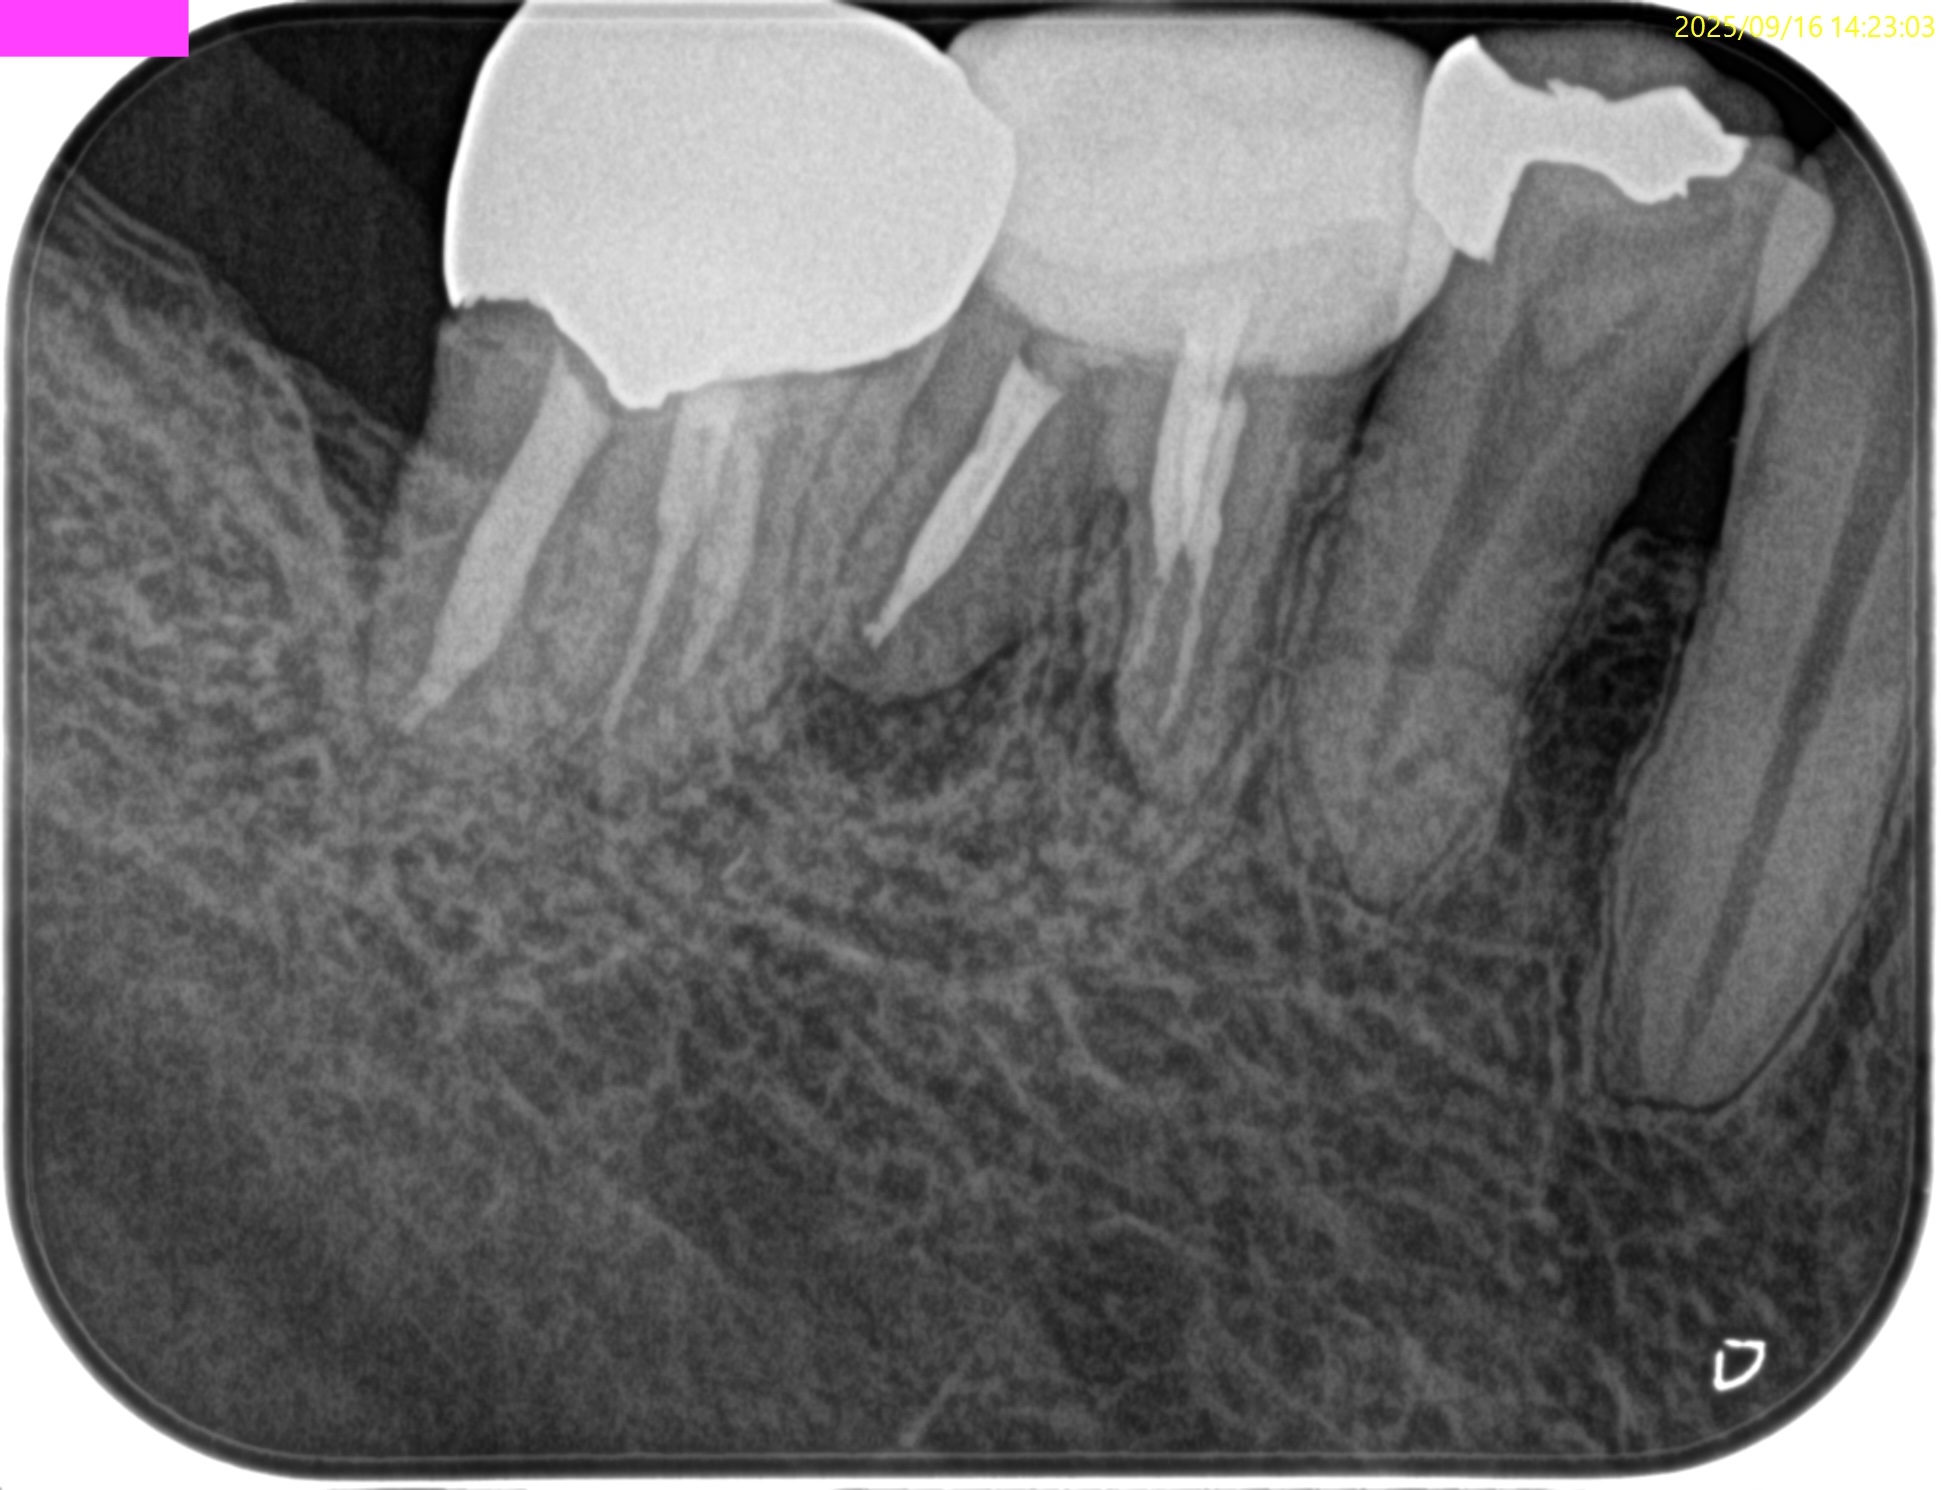

PA(2025.9.16)

根管充填はかなり粗である。

再根管治療でマネージメントが可能そうだ。